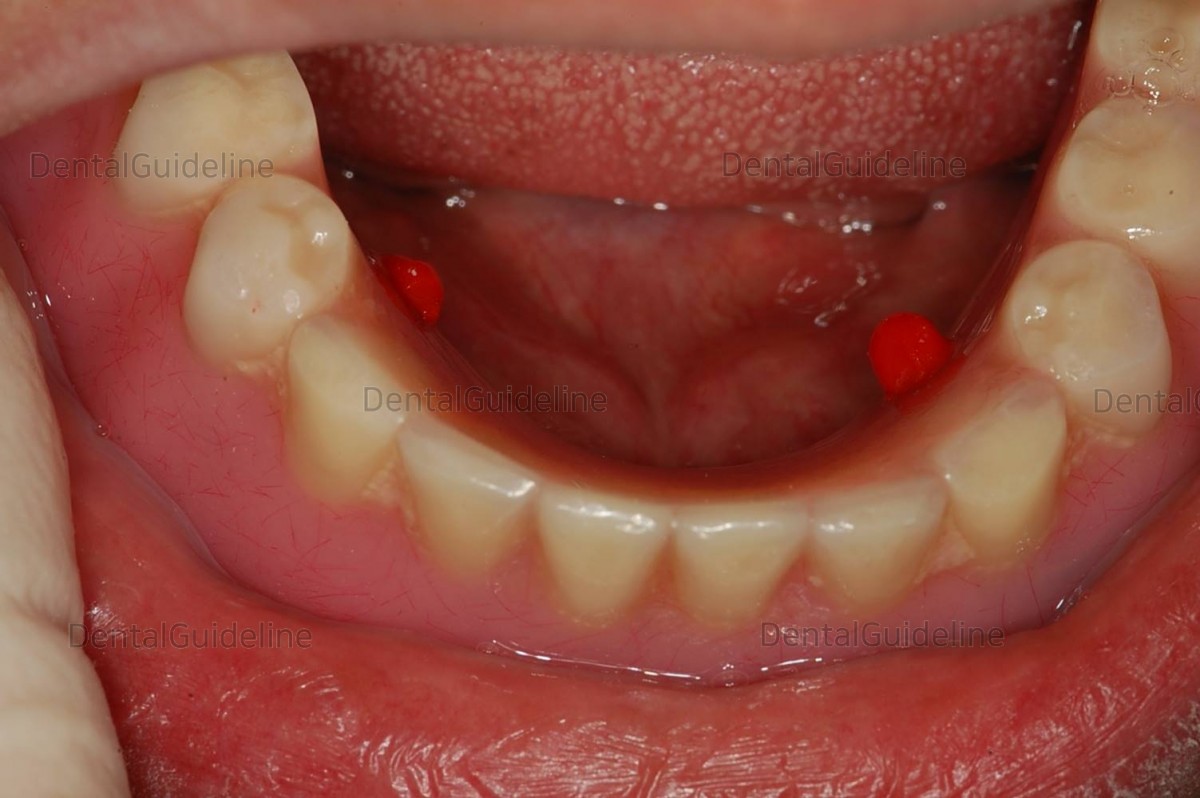

2 weeks after implant uncovery

To secure the locator's space, the denture's inner side was removed by grinding.

escape hole

The LOCATOR abutment was rightened according to the connection manual. the diameter of the implant was ф3.5mm